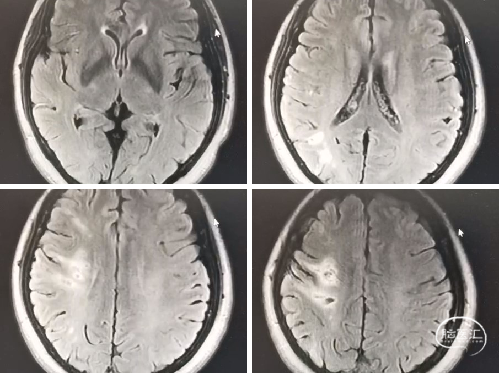

术前影像学检查

颅脑MRI(外院,1月前):脑内多发梗塞灶及软化灶。

颅脑DWI(外院,1月前):右侧颞叶急性脑梗死。

颅脑ASL(入院后):右侧大脑中动脉供血区低灌注。